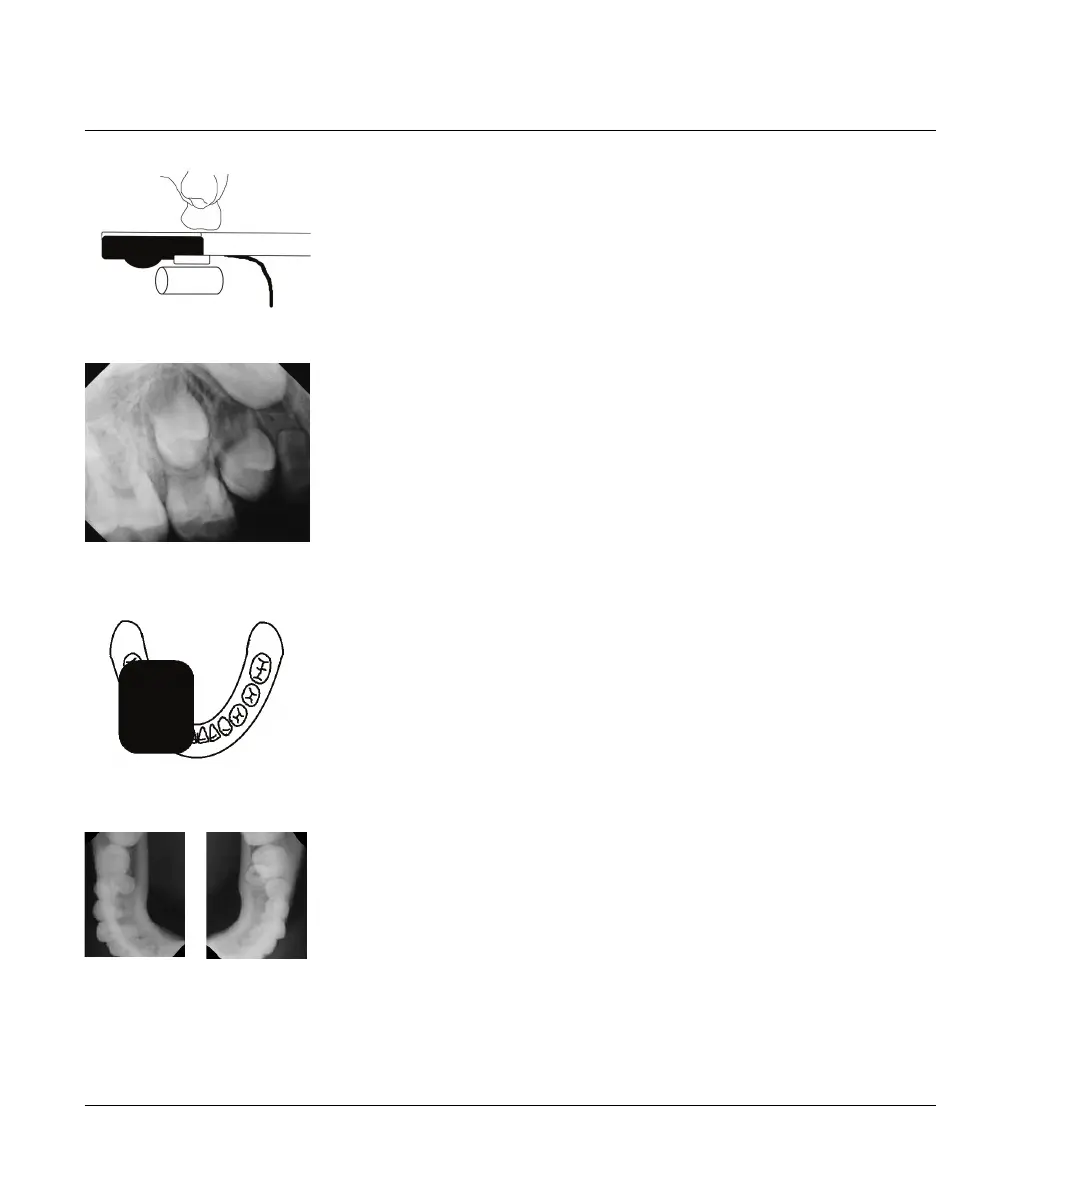

Modifizierte Okklusal-Technik

Platzieren Sie den Sensor parallel zur Okklusalebene und legen Sie eine

Watterolle zum Schutz, Komfort und zur Unterstützung des Patienten ein.

Fordern Sie das Kind auf, den Mund vorsichtig zu schließen. Nehmen Sie

die Röntgenaufnahme mit der Standard-Winkelhalbierungstechnik auf.

Zwei Belichtungen

In manchen Fällen müssen Sie den Sensor der Breite nach von anterior

nach posterior in einer Hälfte des Zahnbogens platzieren und diesen

Prozess dann für die andere Hälfte wiederholen.

In beiden Fällen wird der Sensor parallel zur Okklusalebene platziert und

eine Watterolle wird zum Schutz, Komfort und Unterstützung des Patienten

eingelegt. Fordern Sie das Kind auf, den Mund vorsichtig zu schließen.

Nehmen Sie die Röntgenaufnahme mit der Standard-Okklusaltechnik auf.